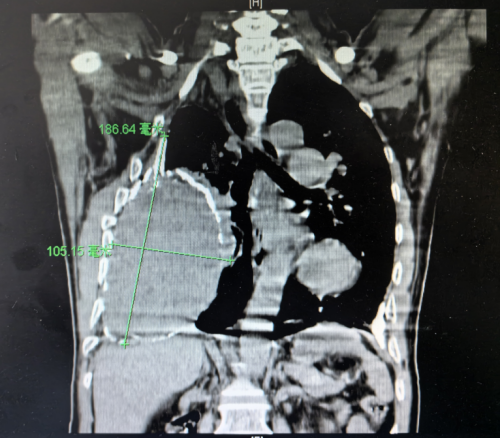

)胸外科、心脏大血管外科,科室主任、主任医师袁跃西查看了张根水的胸部CT,清晰可见他的右侧胸腔存在一个巨大的慢性包裹性脓胸,因为病程长,病灶迁延不愈,包裹的纤维板已经钙化为一层厚厚的硬壳,脓腔里还有18×10cm机化的坏死组织,宛如一个“硬壳鸵鸟蛋”塞进了他的胸腔。

术前CT

袁跃西告诉患者及家属,根据CT显示,包裹性脓胸已经严重压迫到患者的右肺组织,阻碍了肺的扩张,使肺功能受到限制,所以患者一活动就喘不上气。“这是由结核杆菌感染后未规范治疗、迁延不愈造成的慢性脓胸。”袁跃西介绍,患者三十年前确诊结核性胸膜炎,吃了6个月的抗结核药后症状消失,就没有再复查和规范治疗,“当时症状是没有了,但结核病灶并没有完全被‘杀死’,导致结核性胸膜炎迁延不愈,形成包裹性脓胸。”如果持续发展,随着脓腔里的坏死机化组织不断累积,脓腔会越来越大,右肺可能因受压萎缩失去功能,还可能造成纵膈左移压迫对侧脏器,使患者呼吸衰竭,甚至出现更多并发症而危及生命。